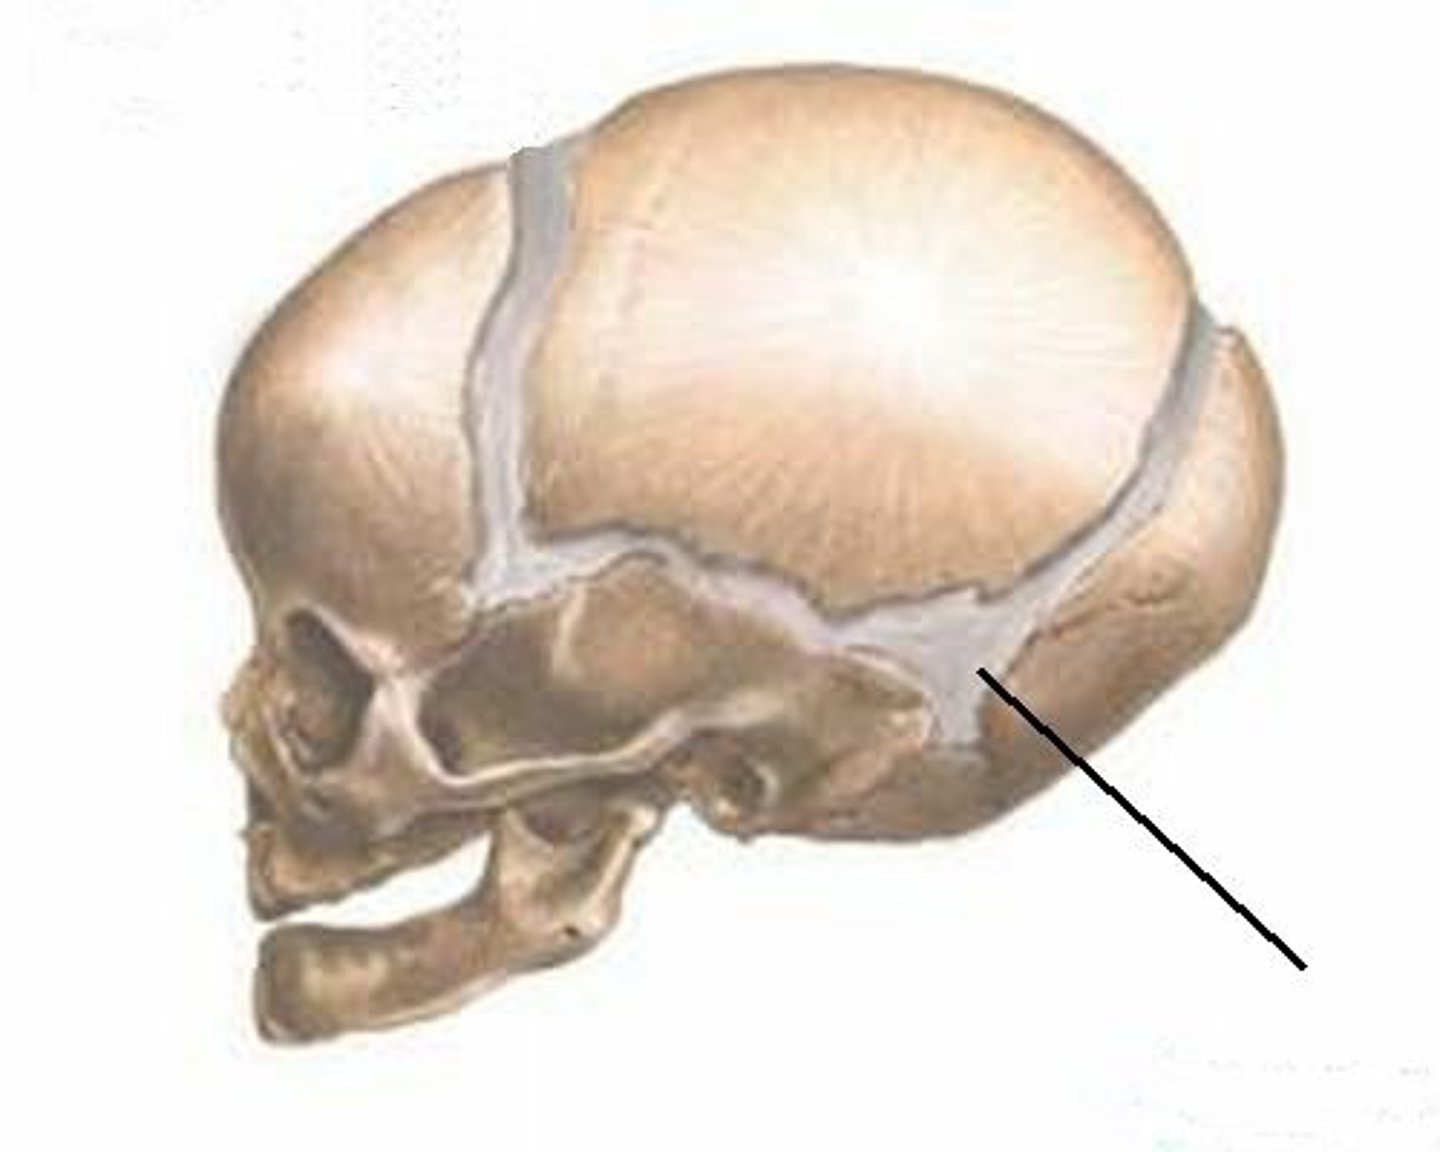

squamosal suture

lambdoidal suture